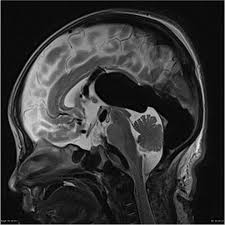

chiari malformation

I: downward displacement of cerebellar tonsils, often associated with syringomyelia

II: downward displacement of medulla, 4th ventricle and cerebellum through foramen magnum, often associated with myelomeningocele

imaging findings in intracranial hypotension

sagging brainstem

downward displacement of cerebellar tonsils